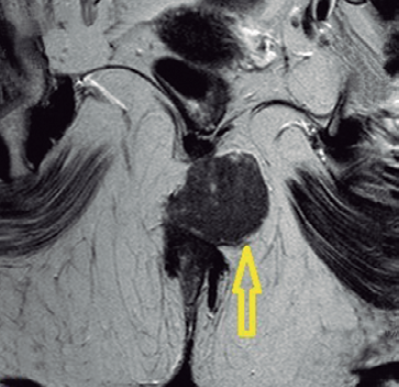

A los 2 meses, misma sintomatología objetivándose tumoración con signos de flogosis pero sin salida de material purulento tras exploración quirúrgica. Se solicita resonancia pélvica en la que se halla una masa heterogénea que se origina en canal anal de 55 por 48 mm, que se extiende por el espacio perineal posterior en contacto con la vertiente posterolateral del musculo puborectal (Figuras1a y 1b).